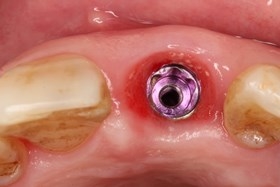

因美觀問題,採取拔牙後立即植牙。(此種治療方式須經醫師評估)

植牙後,立即利用舊牙套轉換成臨時性假牙。